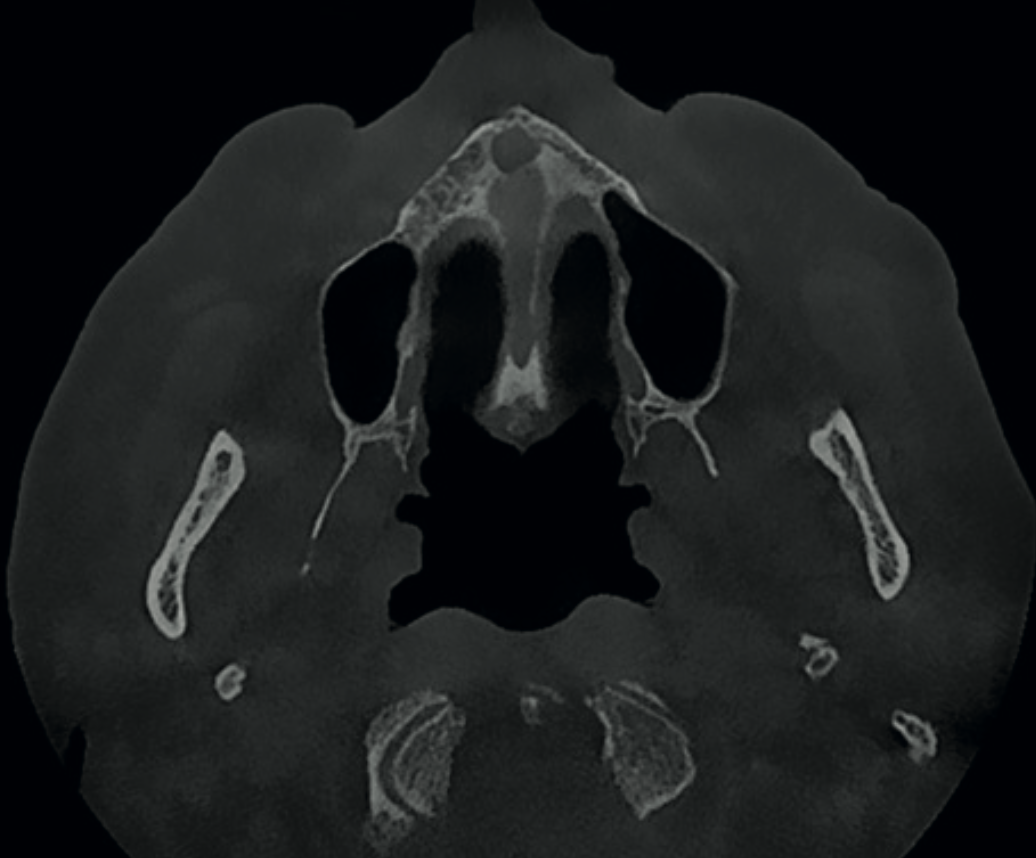

Axial CBCT view showing enlarged incisive foramen suggestive of incisive canal cyst

Finding 1

Enlarged incisive foramen

Larger than usual dimensions on the axial view, possibly indicating an incisive canal cyst. If symptomatic or progressive, this would require surgical intervention.